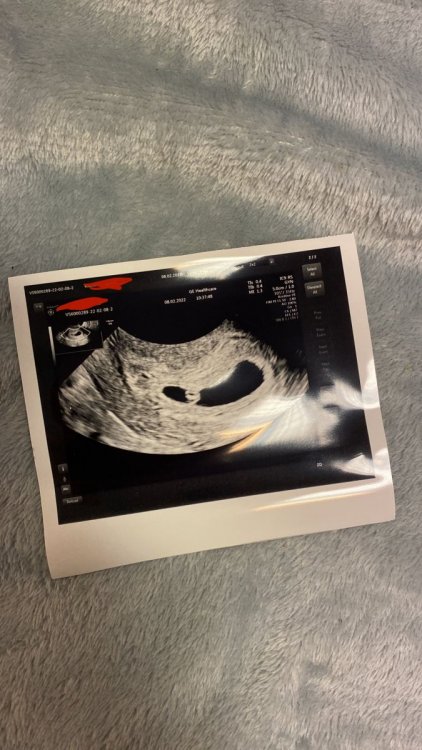

Witam. Ja mam termin na 21.09.2022 :) Na ostatniej wizycie 11.02 słyszałam bicie serca 😊 póki co wszystko w porządku poza tym że mam 2 mięśniaki ale nie powiększają się i według mojej ginekolog nie będą przeszkadzały dziecku..

Witam . W dniu 28.02.22 o 21 miałam robione badania beta HCG wynik 2mlU zgłosiłam to lekarzowi który stwierdził że to początek ciąży , 2 dni później poszłam do innego który stwierdził że to nie ciąża bo ciąża jest ponad 5 mlU wykonałam 04.03 .22 kolejne badania ok 10 rano po pobraniu krwi dostałam silnych skurczy i krwawienia które trwało 2 dni zaobserwowałam że ciągle leciały skrzepy krwi.Tego samego dnia dowiedziałam sie że mój 2 wynik bety to 0,1 mlU mam 21 lat mam stałą pracę , i stałego partnera,z którym staram się o dziecko. Mam mętlik w głowie bo lekarze mówią każdy co innego , na internecie dużo czytałam że to mogła być wczesna ciąża koleżanki też twierdzą że to ciąża . Miałam wiele objawów ciąży ... Bardzo proszę o radę i jakieś informacje co mam w takiej sytuacji robić . Czy powtórzyć badania , czy to było poronienie czy byłam w tej ciaży czy jest szansa że dalej w niej jestem